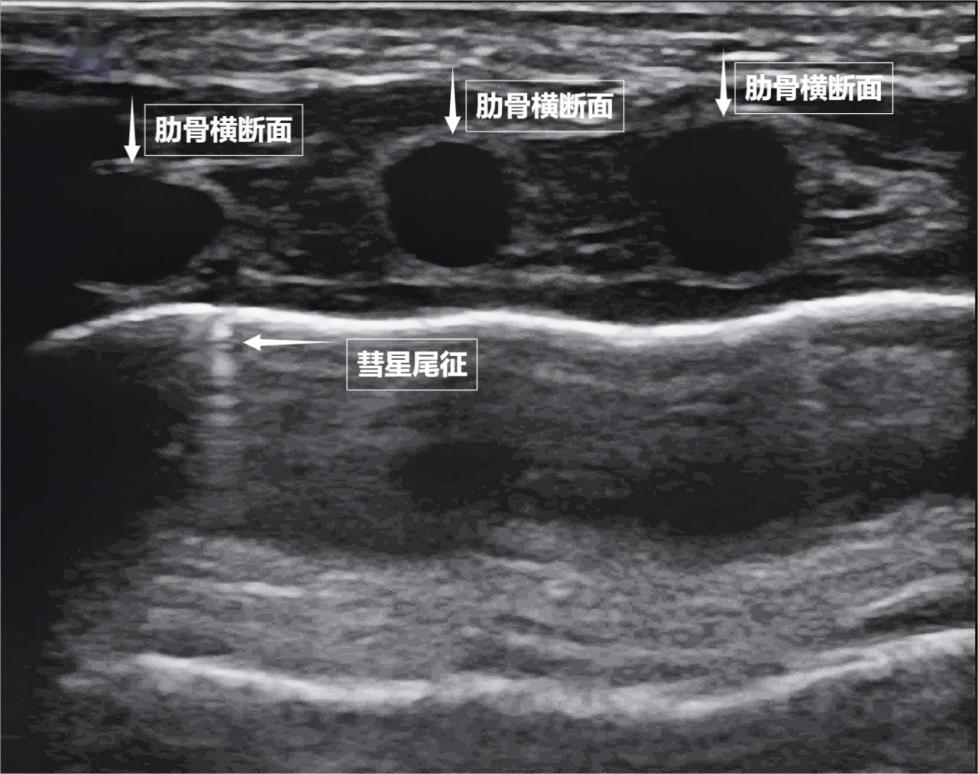

如果我們把超聲圖像調成實時動態模式,把“照片”變成“電影”,更神奇的一幕出現了。隨着呼吸,胸膜線會隨胸廓運動輕柔滑動,這就是“肺滑動徵”。它意味着肺與胸壁正緊密相依、自由順暢地呼吸。若肺與胸壁間有氣胸或胸腔積液,這種滑動會消失。有時,在胸膜線下方還會出現細小的亮白色閃爍點,稱爲“彗星尾徵”(見下圖)。其少量、孤立出現時,通常是正常肺小葉間隔的反射,無需擔心。

圖爲正常新生兒肺部超聲表現